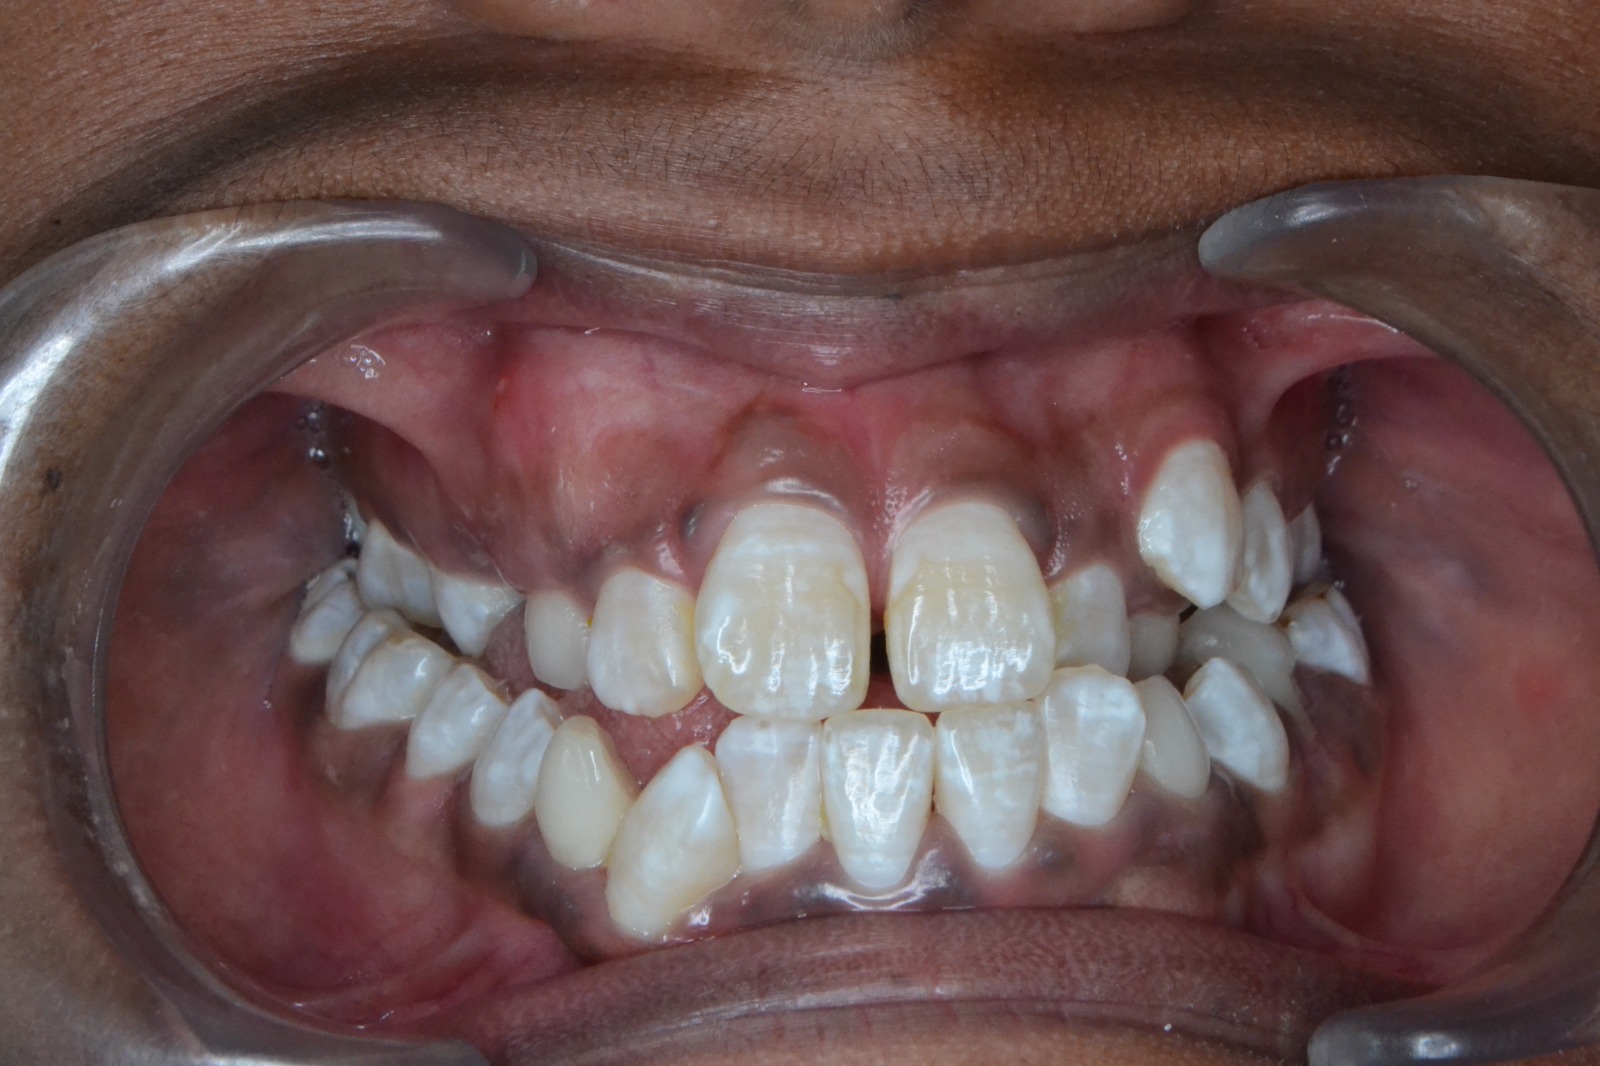

After/Before

See stunning smile transformation before and after

Before After